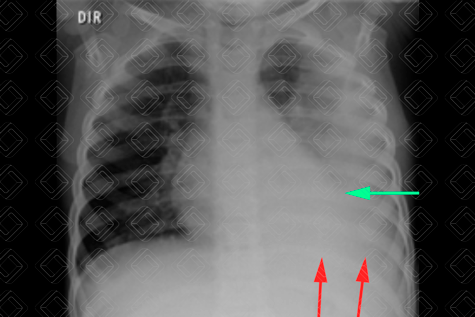

Texto alternativo para a imagem Figura 1. Créditos: Dra. Elazir Mota - Rio de Janeiro/RJ

Descrição das figuras 1 e 2: Na radiografia de tórax AP observa-se uma opacidade que apaga o contorno cardíaco à esquerda (seta verde) e o diafragma esquerdo (setas vermelhas). No estudo em perfil, evidencia-se somente um diafragma (setas amarelas). Fica a dúvida se há somente pneumonia ou pneumonia associada a derrame. O próximo passo na população pediátrica é fazer uma ultrassonografia de tórax.

• Radiografia de tórax AP ou PA + perfil: Exame de escolha na população pediátrica, mas, diante da suspeita de derrame pleural, idealmente deve ser complementado com a ultrassonografia do tórax (lembrando que a avaliação de derrame pleural com a incidência radiográfica em Laurell - decúbito lateral com raios horizontais - está em desuso);